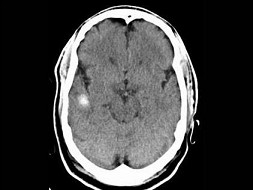

男,54岁,癫痫发作,结合图像,最可能的诊断是()

A.脑脓肿

B.脑出血

C.海绵状血管瘤

D.胶样囊肿

E.脑转移瘤